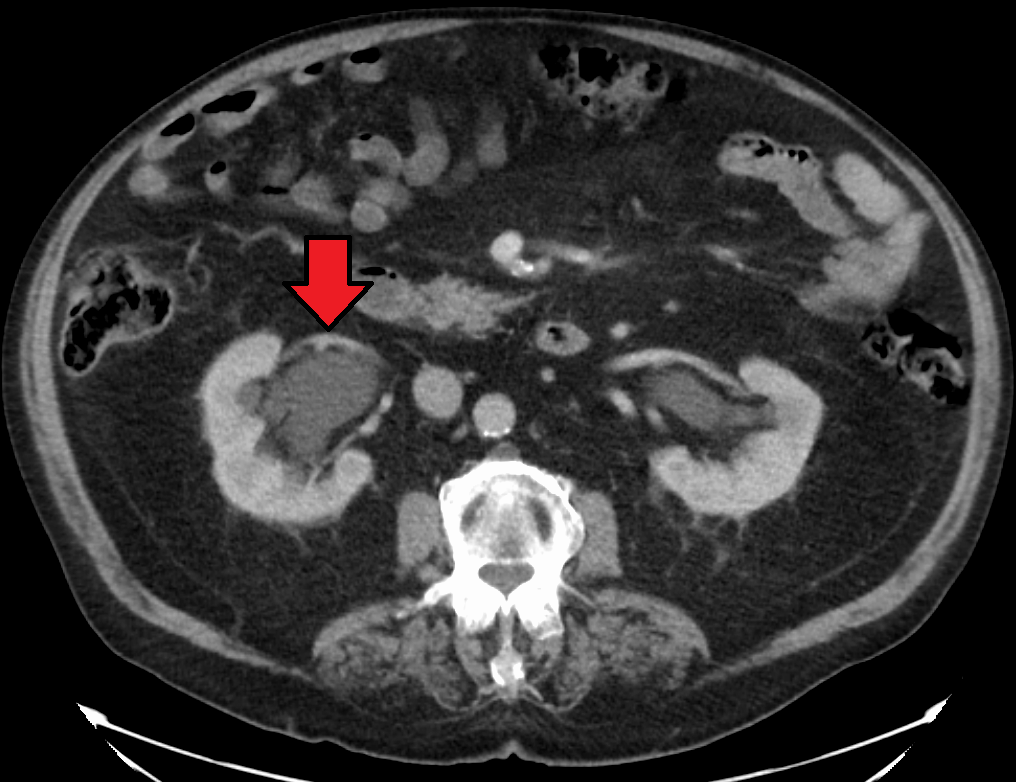

질병을 진단하려면 환자의 병력과 기타 신체 검사 정보를 알아야 한다. 이는 일부 영상 검사를 동반해야 한다. 일반적으로 초음파 검사를 사용하여 환자의 요로, 콩팥 등의 상태를 확인할 수 있다. 또한 CT 스캔과 MRI는 요로 및 폐쇄를 보다 명확하게 보여줄 수 있다.[8]

정맥 신우 조영술(IVU), 신장 초음파 검사, CT, MRI 등의 영상 검사도 중요하다. 초음파 검사는 요관과 신장을 시각화하고 수신증 및 수뇨관증 유무를 확인하는 데 유용하며, IVU는 막힘의 해부학적 위치 평가에 유용하다. 순행 또는 역행 신우 조영술은 IVU와 유사한 소견을 보이면서 치료 옵션도 제공한다. 실시간 초음파와 도플러 초음파 검사는 혈관 저항 검사와 함께 폐색이 요로 기능에 미치는 영향을 파악하는 데 도움이 된다.[12]

신 산통(소변에 혈흔이 섞인 옆구리 통증)의 초기 검사는 나선형 또는 헬리컬 CT 스캔이다. 이는 소변 흐름 폐색 여부와 다른 신장 기능도 보여준다. CT는 대부분의 결석을 확인할 수 있어 초기 검사로 흔히 선택되지만, 임신과 같이 방사선 노출을 피해야 하는 경우에는 사용하지 않는다.[13][14] 우연히 발견된 산전 수신증의 경우, 첫 검사는 산후 신장 초음파 검사다. 산전 수신증의 많은 사례가 자연적으로 해결되기 때문이다. 출생 후 며칠 이내에 시행하지만, 너무 이른 검사는 경미한 수신증을 놓칠 수 있어 4~6주 후 추적 초음파 검사를 권장하기도 한다.[15] 배뇨 방광 요도 조영술(VCUG)은 방광 요관 역류나 후부 요도 판막 같은 해부학적 이상을 배제하기 위해 시행된다. 수신증이 심각하고 요관 신우 접합부(UPJ) 또는 요관 방광 접합부(UVJ) 폐색이 의심되면, MAG-3 스캔과 같은 핵 영상 검사가 필요하다.[13]